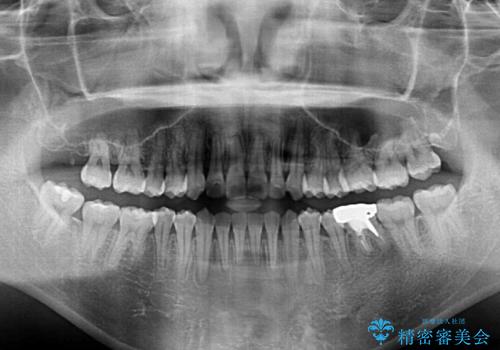

奥の銀歯も気になっていたため、矯正治療後にセラミッククラウンにて補綴することとしました。

1年半程度の期間を見込んでいましたが、上下の真ん中の位置をできる限り合わせるための調整に少し時間がかかってしまいました。

咬み合わせが安定し、前歯の汚れも付きにくくなりました。